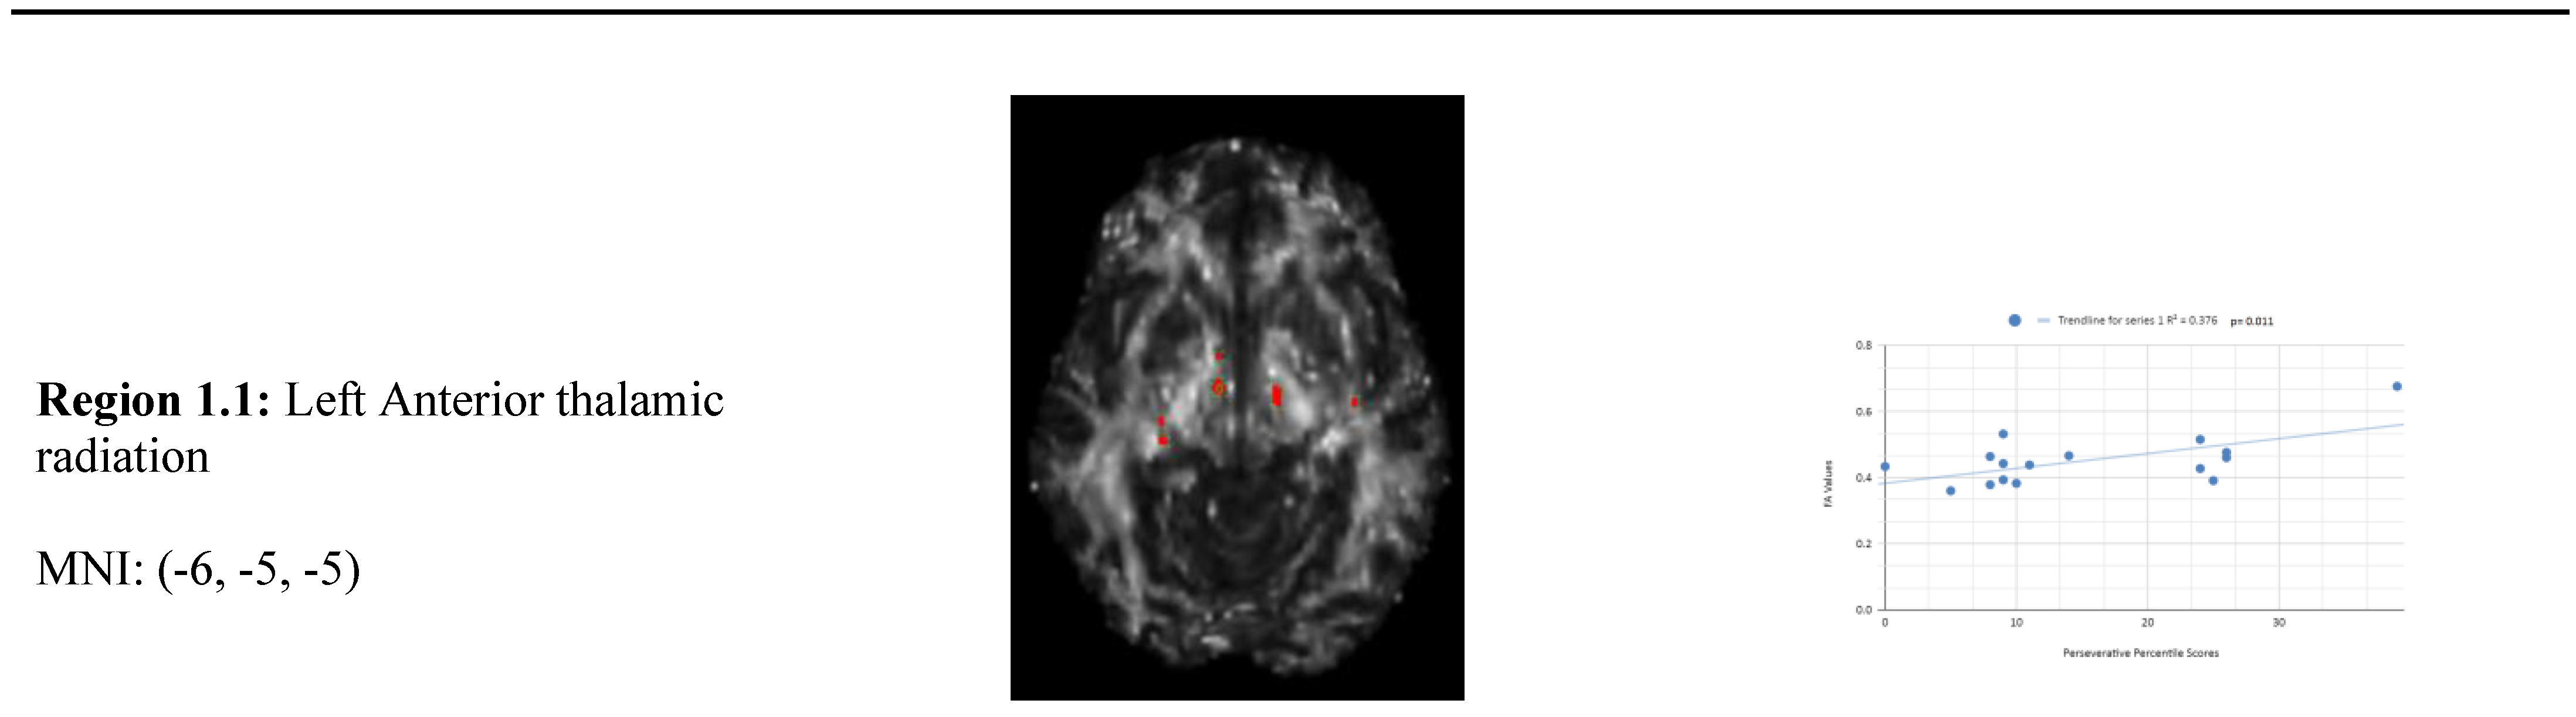

Variance analysis indicated significant group differences across perseverative response, non-perseverative response, and conceptual response categories. We observed a statistically significant relationship between the mean WCST perseverative percentile score of the chronic mTBI patient subjects, which was 15.27 ± 6.03 compared to the mean standard control WCST perseverative percentile score of 87.6 ± 9.85. There was a statistically significant positive linear relationship between reduced percentile scores for perseverative error and reduced FA in the left anterior thalamic radiation, right cingulate gyrus, and right superior longitudinal fasciculus regions (See Figure 1). No statistically significant negative correlations were observed in the perseverative response category.

Figure 1 shows transaxial images of key brain regions of interest including the Anterior thalamic radiation (ATR), Cingulate Gyrus, and Pre-Central Gyrus. It also shows FA values of each region correlated with perseverative response percentile scores through linear regression plots. In the X-axis, perseverative percentile scores are depicted. In the Y-axis, FA values are depicted. Reduced FA values are consistent indicators of TBI, and reduced perseverative percentile scores are associated with higher errors and poorer performance which is associated with cognitive impairment. A consistent positive association in 4 out of 4 correlations in this category validates the premise of the hypothesis that a decrease in FA results in poorer performance on the WCST.

In the perseverative response (Ep) category, 2 statistically significant positive correlations are displayed between perseverative percentile scores and FA values in the left and right frontotemporal and frontal-posterior white matter regions derived from positive z-maps. These regions include regions 1.1 (Left Anterior thalamic radiation) and 1.2 (Left Anterior thalamic radiation) on the bottom left panel shown above. Regions 1.3 (Right Cingulate Gyrus) and 1.4 (Right Pre-Central Gyrus) are shown on the bottom right panel. The positive correlations in these specific regions suggest that as perseverative percentile scores decrease, FA values also decrease. DTI FA data is validated by WCST perseverative percentile score data in the anterior thalamic radiation, cingulate gyrus, and superior longitudinal fasciculus.